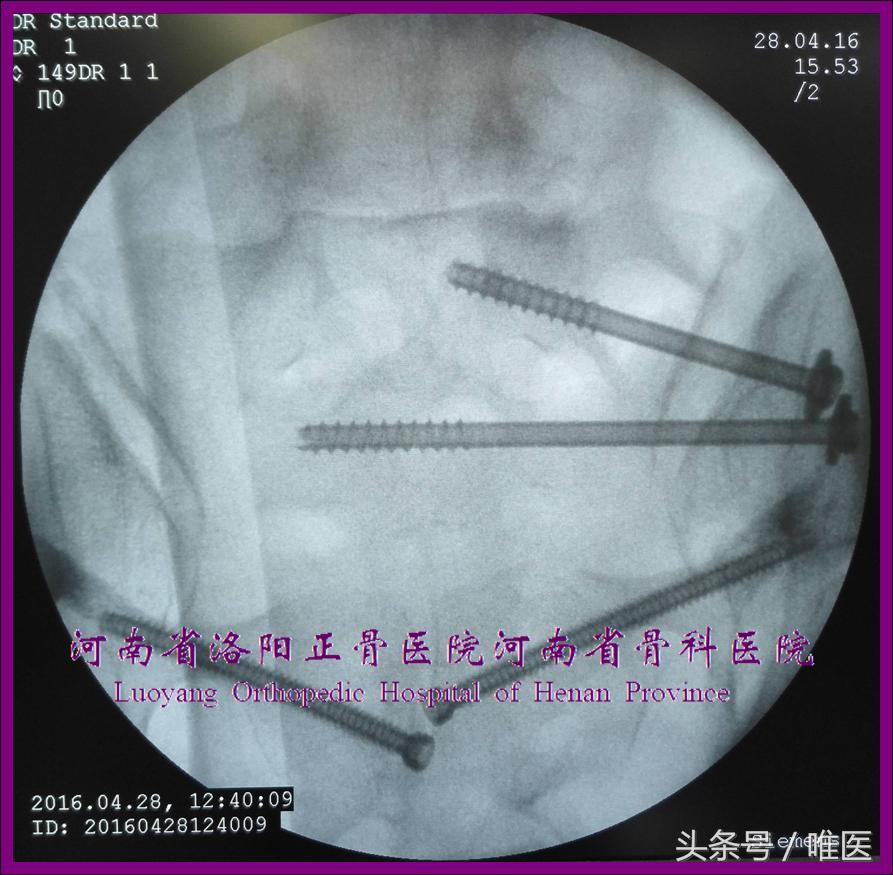

一般情况下,治疗SIJ脱位和骨折脱位的骶髂螺钉多为斜向、部分螺纹,治疗骶骨骨折的骶髂螺钉多为平向、全螺纹;骶1骶髂螺钉可斜向或平向(需根据上骶段的类型及置钉通道的大小而定)置入,骶2骶髂螺钉为平向(如有置入空间);在置入第一枚骶髂螺钉固定SIJ脱位或骶骨骨折后,最好再置入一枚全螺纹骶髂螺钉作为位置螺钉加强固定,从而实现骨盆后环的两点固定(two-pointed stabilization)[10]。(图1)

图1. 骶髂螺钉的类型及“两点固定”示例。